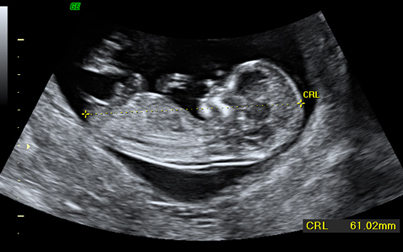

Ecografía de primer trimestre (semanas 11-14). Su objetivo básico es identificar el número de fetos (gestación única o múltiple), su vitalidad (latido cardíaco) y su tamaño (mediante la longitud cráneo-caudal). Durante esta ecografía se determinan una serie de parámetros que determinan un riesgo determinado para síndrome de Down y otras patologías cromosómicas, como la translucencia nucal, el hueso nasal o el flujo sanguíneo fetal. Estos datos se tienen en cuenta para informar sobre el riesgo de síndrome de Down (denominado screening combinado de cromosomopatías).